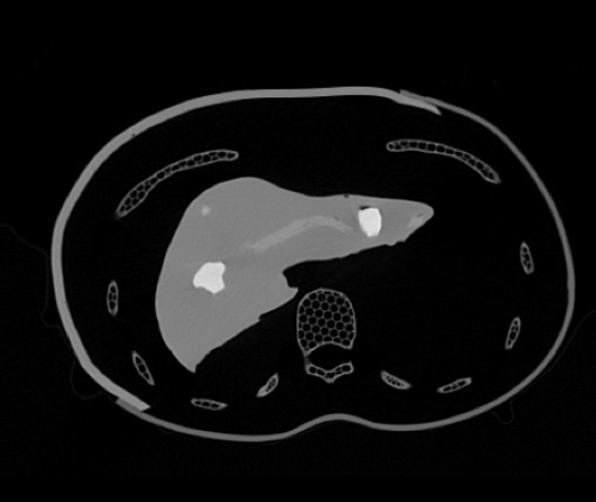

CT培训模体包括: 躯干,皮肤,肋骨,脊柱,肝脏病变,门静脉

CT培训模体有11个不同形状、大小和位置的肝内靶点,可以进行真实的干预训练。其高密度的CT表现有助于治疗前后图像的融合。

肝脏病变清晰可见

•结构:躯干与皮肤,肋骨,脊柱,肝脏病变和门静脉

•肝脏11个病灶

-不同的形状、大小和位置-高密度CT表现